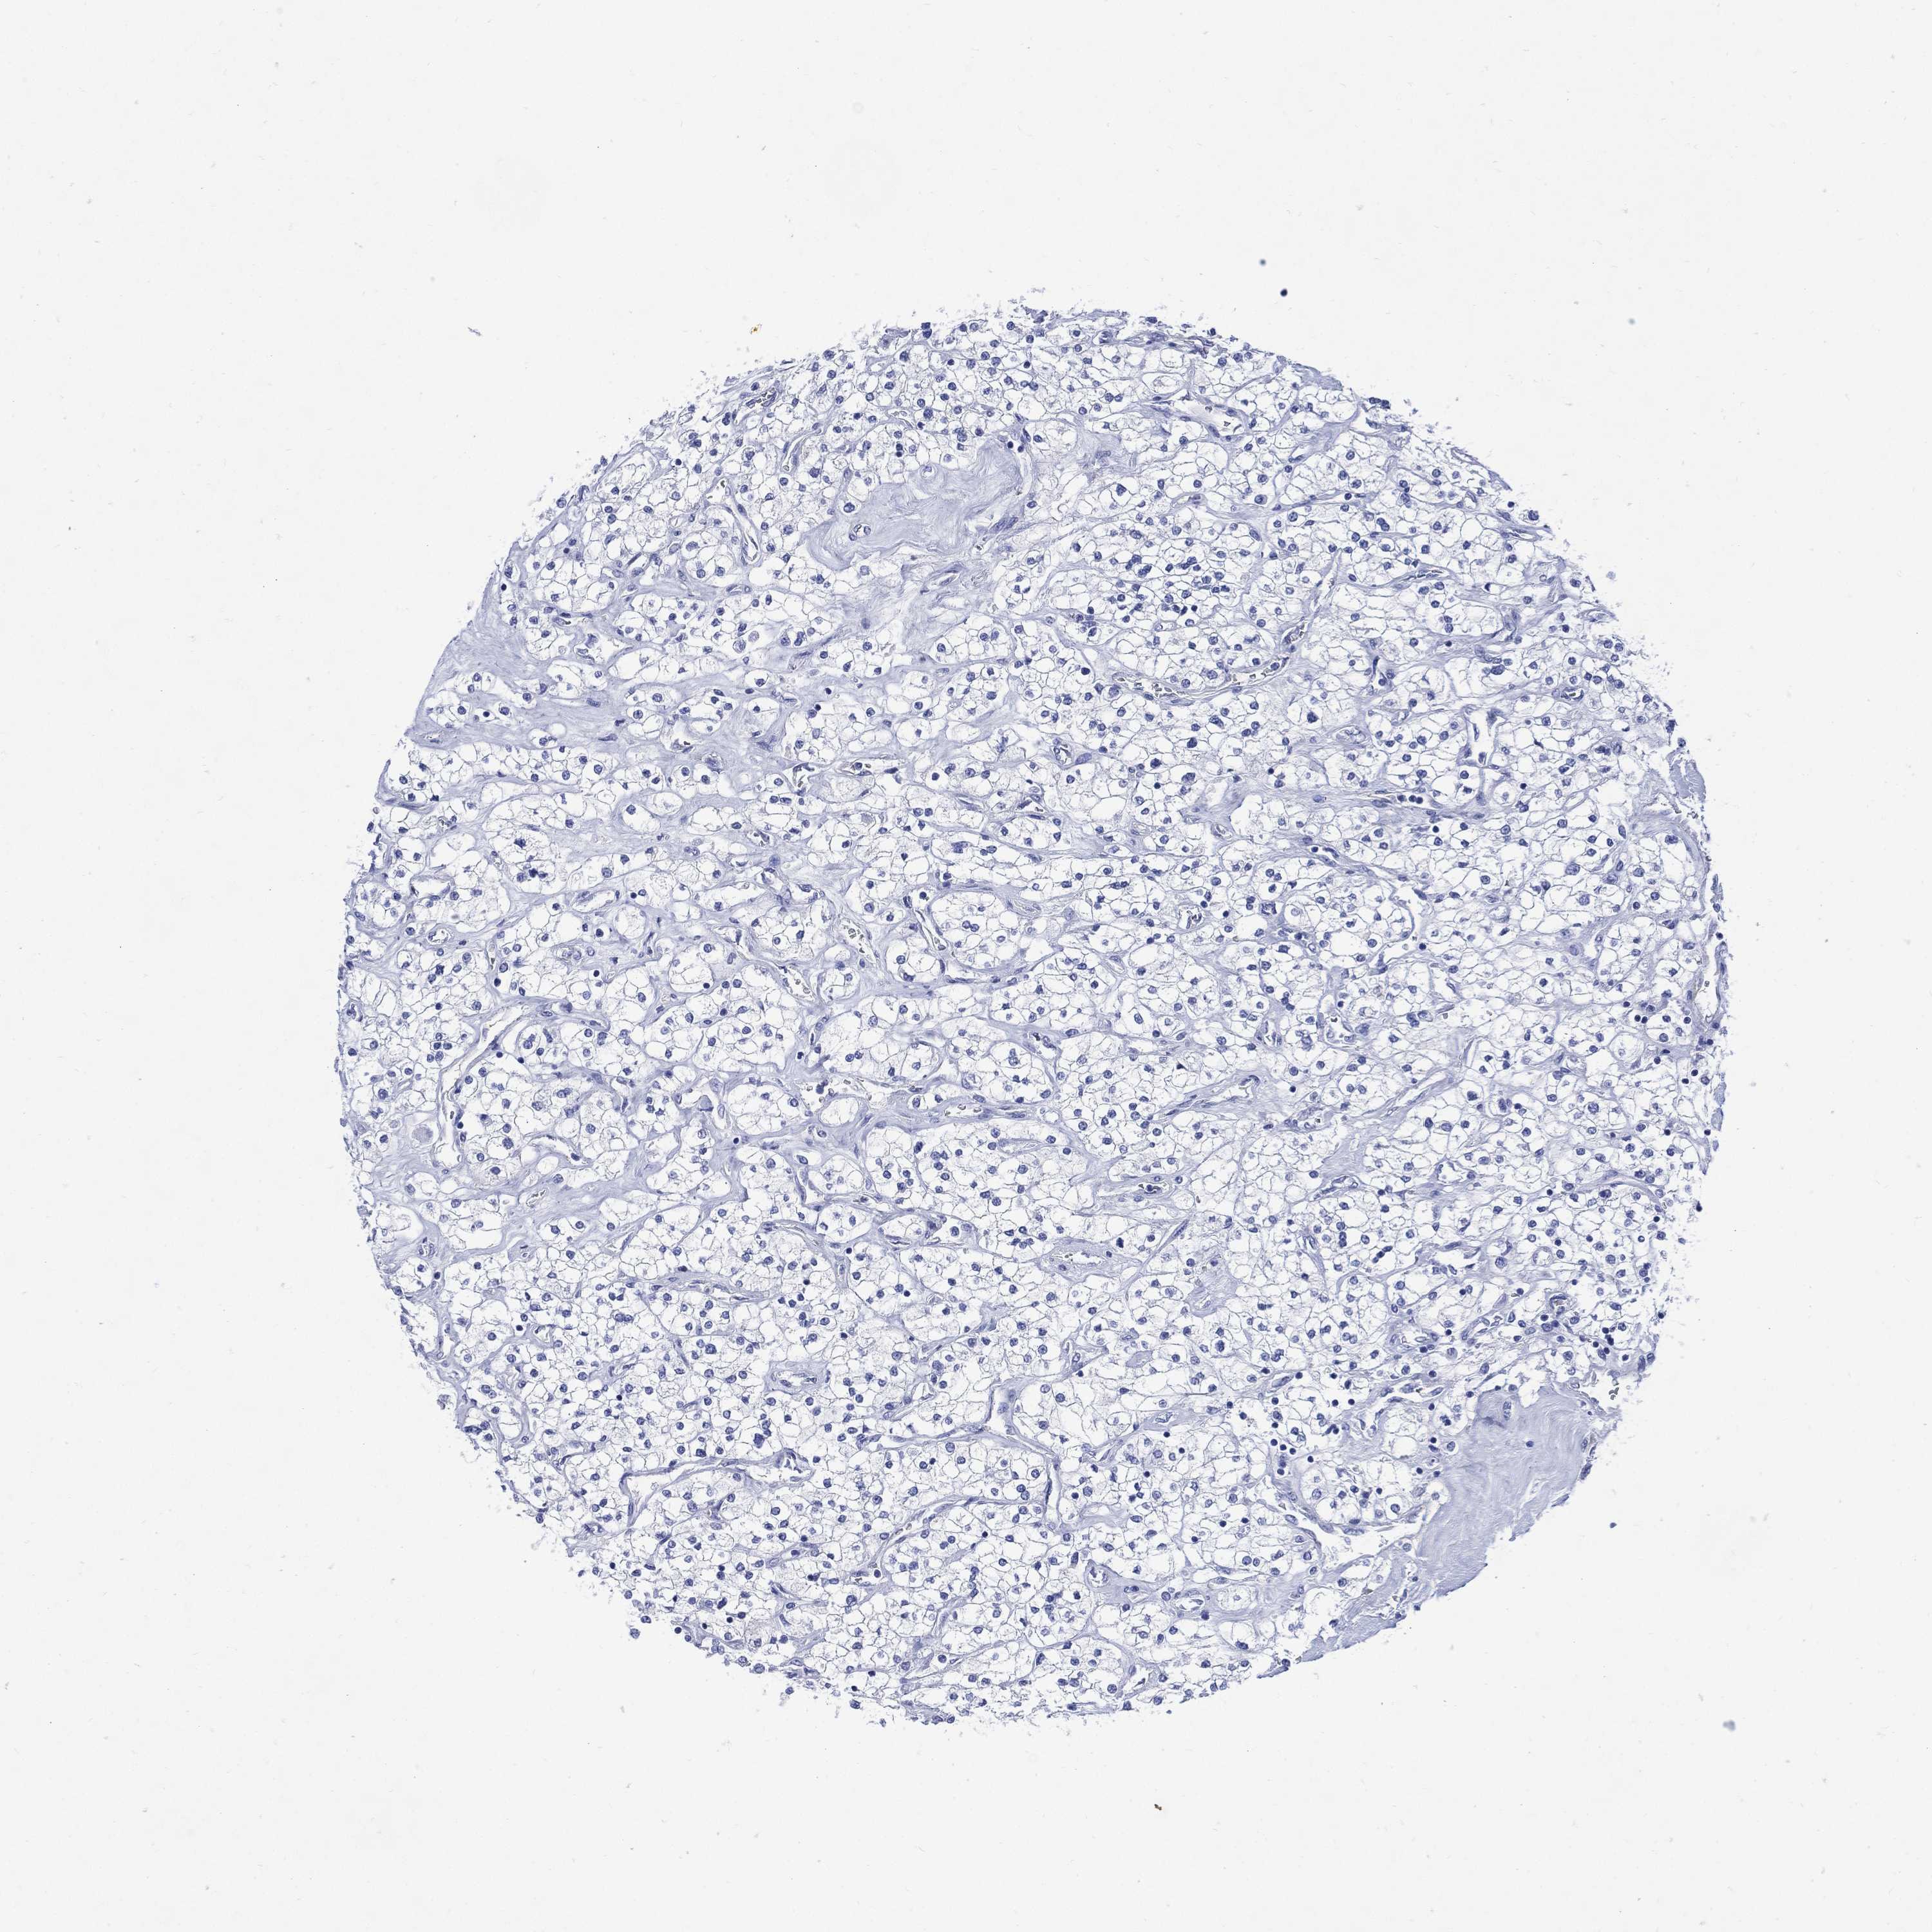

TCGA RNA samplesi

RNA-seq data is reported as average FPKM (number Fragments Per Kilobase of exon per Million reads), generated by the The Cancer Genome Atlas (TCGA) .

Normal distribution across the dataset is visualized with box plots, shown as median and 25th and 75th percentiles. Points are displayed as outliers if they are above or below 1.5 times the interquartile range. FPKM values of the individual samples are presented next to the box plot.

Average pTPM 0.0

Number of samples 64